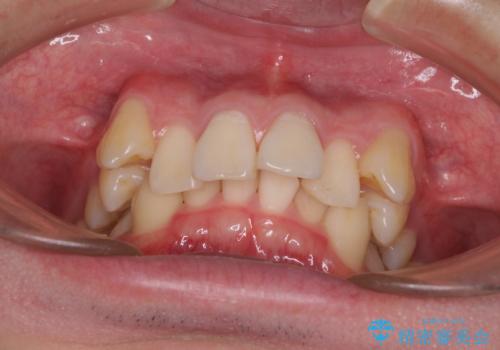

- 八重歯を気にして来院された患者様です。

顕著な上顎の八重歯とディープバイトであったため、上顎の左右第一小臼歯を抜歯することとしました。

犬歯歯根の位置や奥歯の咬み合わせから、ワイヤー装置での治療を強くおすすめいたしましたが、ご本人の強い希望により、妥協的な仕上がりとなることを了解いただき、インビザラインにて矯正治療を行うこととしました。

インビザライン単体で、左右ともに移動の難しい位置に歯根のある犬歯を整えるのは困難と判断し、補助装置を併用することとしました。

ディープバイトや奥歯の咬み合わせなど、インビザライン矯正では限界がありワイヤー装置での治療に及ばない仕上がりとなりました。

ただし、患者様としては八重歯や、それに伴う唇の閉じにくさが改善されたとのことで、納得いく状態での治療終了となりました。